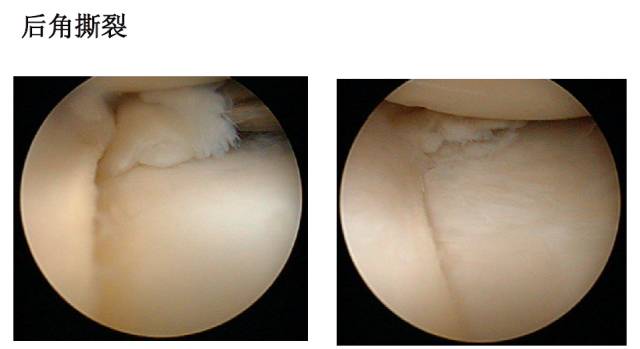

半月板损伤的类型

半月板损伤的处理原则•半月板损伤的治疗取决于半月板撕裂的类型,有3种治疗建议:1)无需治疗的撕裂:急性期病人,或撕裂小于1cm的全层外围撕裂和不完全的纵行撕裂,尤其是发生在外侧半月板时;退行性膝关节病变,应尽力保留稳定的半月板。2)需要修补和重新固定的撕裂:红-红区,或红-白区撕裂3)需要切除的撕裂•一般来讲,病人与年轻,越小的、越新鲜的撕裂,永久愈合的可能性就越大。•能修补尽可能修补•不能修补要尽可能保留半月板组织•必须全切除者应想到半月板重建